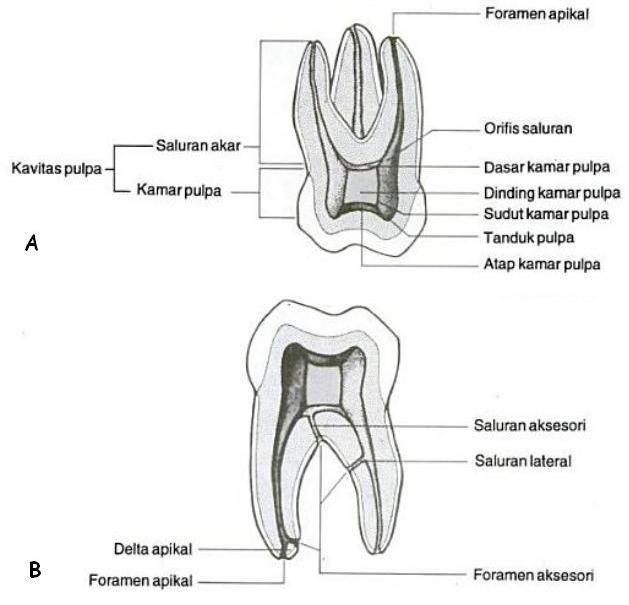

PANJANG SALURAN AKAR GIGI MOLAR PERTAMA PERMANEN RAHANG BAWAH PADA MAHASISWA FAKULTAS KEDOKTERAN GIGI UNIVERSITAS JEMBER ANGKATAN - PDF Free Download

PANJANG SALURAN AKAR GIGI MOLAR PERTAMA PERMANEN RAHANG BAWAH PADA MAHASISWA FAKULTAS KEDOKTERAN GIGI UNIVERSITAS JEMBER ANGKATAN - PDF Free Download

BAB 2 TINJAUAN PUSTAKA - PDF Download Gratis

BAB 2 TINJAUAN PUSTAKA - PDF Download Gratis

BAB 2 TINJAUAN PUSTAKA 2.1 Definisi Gigi Impaksi Gigi impaksi merupakan gigi yang tidak dapat muncul sepenuhnya ke dalam rongga

UNIVERSITAS INDONESIA JUMLAH DAN BENTUK AKAR SERTA KONFIGURASI SALURAN AKAR GIGI MOLAR SATU RAHANG ATAS DAN BAWAH DI JAWA BARA